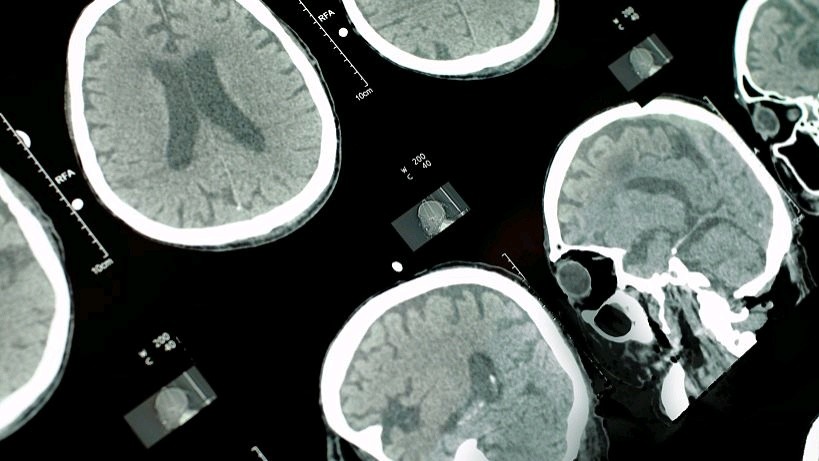

想了解冠脉造影技术,就要了解一下什么是冠心病。冠心病是指冠状动脉处长了斑块,这些斑会不断的膨胀,不断的成熟,让整个冠状动脉变得狭窄,让血液无法流入心脏。冠心病会逐渐导致人患上心绞痛,心肌梗死和心源性猝死。

冠状动脉检查在心脑血管疾病的检测和预防上做出了许多的贡献,也是医学界中的一个里程碑,它能够帮助主治医生和医学者更好的了解病人内部的状况。同时也帮助患者知晓身体状况,知晓心脑血管疾病真正的状态。